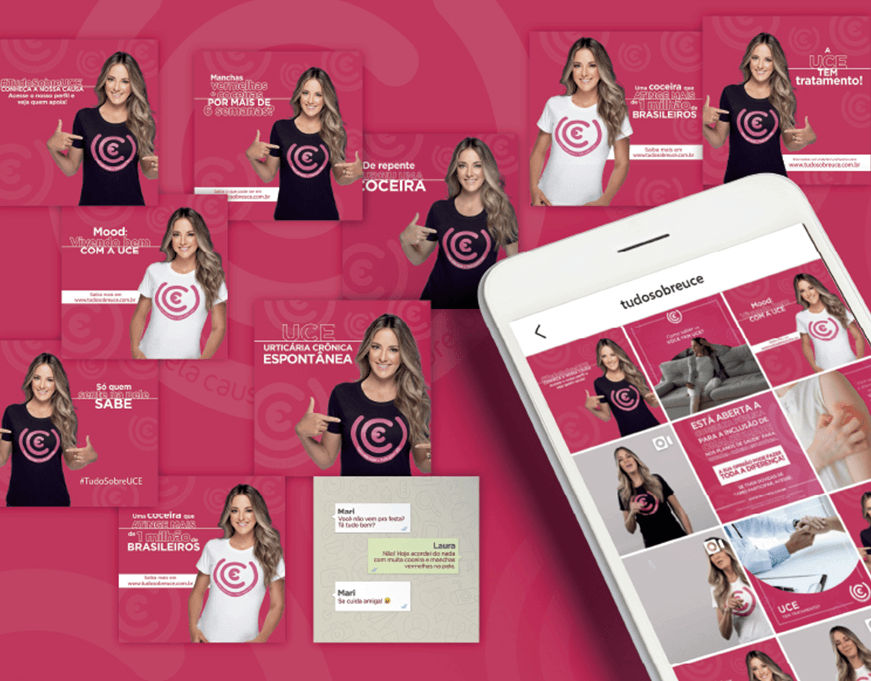

Publicidade

Focados no mercado B2C, atuamos na criação de marcas e campanhas on e off.

Meta Ads

Gestão de redes sociais

Tráfego pago